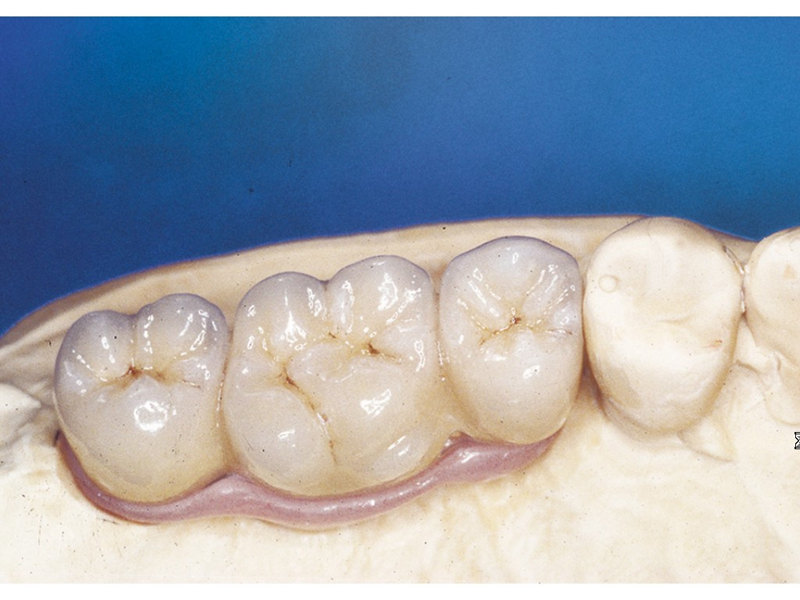

Protetické řešení může být pomocí můstku, který je kotvený na implantátech nebo pomocí jednotlivých korunek na implantátech.

V zásadě je možné do těchto můstků zařadit i přirozené zuby, zejména pokud je potřeba tyto zuby ošetřit proteticky

- korunkami. Korunky nebo můstky mohou být na implantáty nacementovány nebo přišroubovány.

Zdravé zuby zůstanou zachovány a přitom náhrady jsou pevné, jako na vlastních zubech